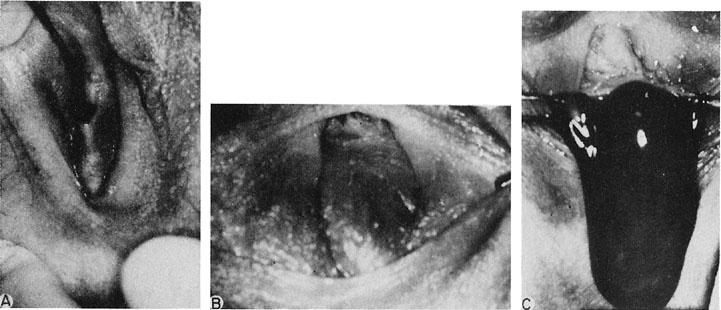

Unobstructed failure of lateral fusion involving both the uterus (didelphic) and the vagina is usually without symptoms; nevertheless, the narrowness of the vagina may result in significant dyspareunia when coitus is attempted (Fig. 15). This may require the removal of the vaginal septum. The vaginal septum is often thick. Complete resection of the septum is not necessary because the tissue often retracts and is not visible as a ridge. Generous pedicles should be taken such that hemostasis is ensured, avoiding troublesome bleeding. Reproduction is modestly compromised in patients with didelphic uteri. Unfortunately, information is anecdotal and consists of case reports or small series recording examples of primary infertility, pregnancy wastage, and premature labor. There is no indication for surgical intervention in a didelphic condition except for removal of a vaginal septum that might cause dyspareunia.

Fig. 15. A. A double vagina is noted. B. The hysterogram documents a double uterus with a complete septum.